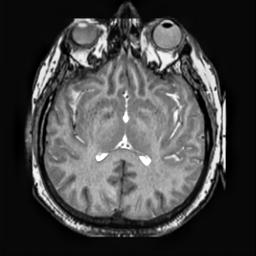

To demonstrate the effectiveness and efficiency of the proposed image fusion method , we conduct a set of comparative experiments on three image datasets. The first is composed by 8 pairs of multi-modal medical images and the second one contains 15 pairs of multi-focus gray or color natural images. These two datasets are often used in many related papers and some examples are shown in Figure 3(a) and Figure 3(b). The third one is a new multi-focus cervical cell image dataset collected by ourselves, which consists of 15 groups of color images and each group contains a series of multi-focus cervix cell images with size of or , etc. Some source examples are shown in Figure 3(c). Our source code implemented in C++ along with the new multi-focus cervical cell image dataset is available online.

We first evaluate the performance of the proposed method under varying total number of octaves and number of layers sampled per octave. The fused images of a pair of multi-modal medical images with different and are shown in Figure 4. In this example, on the one hand, when only 1 or 2 octaves are involved in constructing the DoG pyramid, the fused images fail to keep the integrity information of large size objects (e.g. eyeballs), while by increasing the value of , the integrity information of eyeballs is preserved. On the other hand, although not as significant as the increase of octave numbers , the fused image can contain more details by the increase of layer numbers . The corresponding objective quality metrics are shown in Figure 5. As shown in Figure 5(a), most of the metric values are improved as the number of octaves increases with the fixed layer numbers 3 in the global tendency and each of them tends to be stable when the number of octaves is 5. To get a relatively good quality from Figure 5(b), we can notice that some of the metric values can get a good performance when the number of layers is 3, such as the MI, SSIM, QI and VIF, though there are only a little change of all the metric values by increasing the number of layers with the fixed octave numbers 5. Because it will result in more computation burden with the increase of the value and , and for different kinds of source images, there are different performance with the diverse parameter settings. To get a trade-off between them in our experiments, we set for the multi-modal dataset, for the natural datasets and for the multi-focus cell dataset, respectively.

Figure 6 shows the fused images obtained by different methods with the multi-modal source images shown in Figure 3(a). As shown in these figures, the proposed method can produce images which preserve the complementary information of different source images well. Moreover, due to the scale-invariant structure saliency selection, our method can keep the integrity information of large size objects and the visual details simultaneously. Although the fused image generated by other methods can also capture the details to some extent, all of them fail to keep the integrity information of large size objects such as the eyeballs. Furthermore, from Figure 6(k)-6(t), the DTCWT, GFF, IM and NSCT methods may decrease the brightness and contrast while the proposed method can preserve these features and details without producing visible artifacts and brightness distortions.